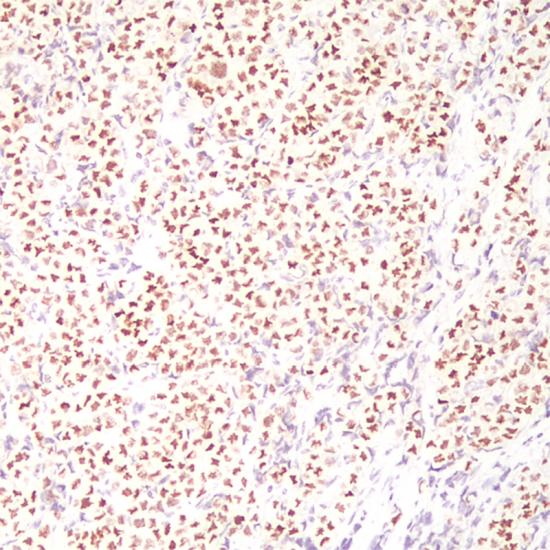

GATA-3

• 陽(yáng)性部位:

細(xì)胞核

• 陽(yáng)性對(duì)照:

乳腺癌

GATA3是一種鋅轉(zhuǎn)錄因子,在許多組織和細(xì)胞類(lèi)型中對(duì)促進(jìn)和引導(dǎo)細(xì)胞增殖、發(fā)育和分化起到重要作用。在乳腺癌和尿路上皮癌高度特異表達(dá)。GATA3表達(dá)于乳腺小葉癌和浸潤(rùn)性導(dǎo)管癌,同時(shí)在乳腺癌中GATA3表達(dá)與ER、PR成正相關(guān)系,與HER-2成負(fù)相關(guān)系。